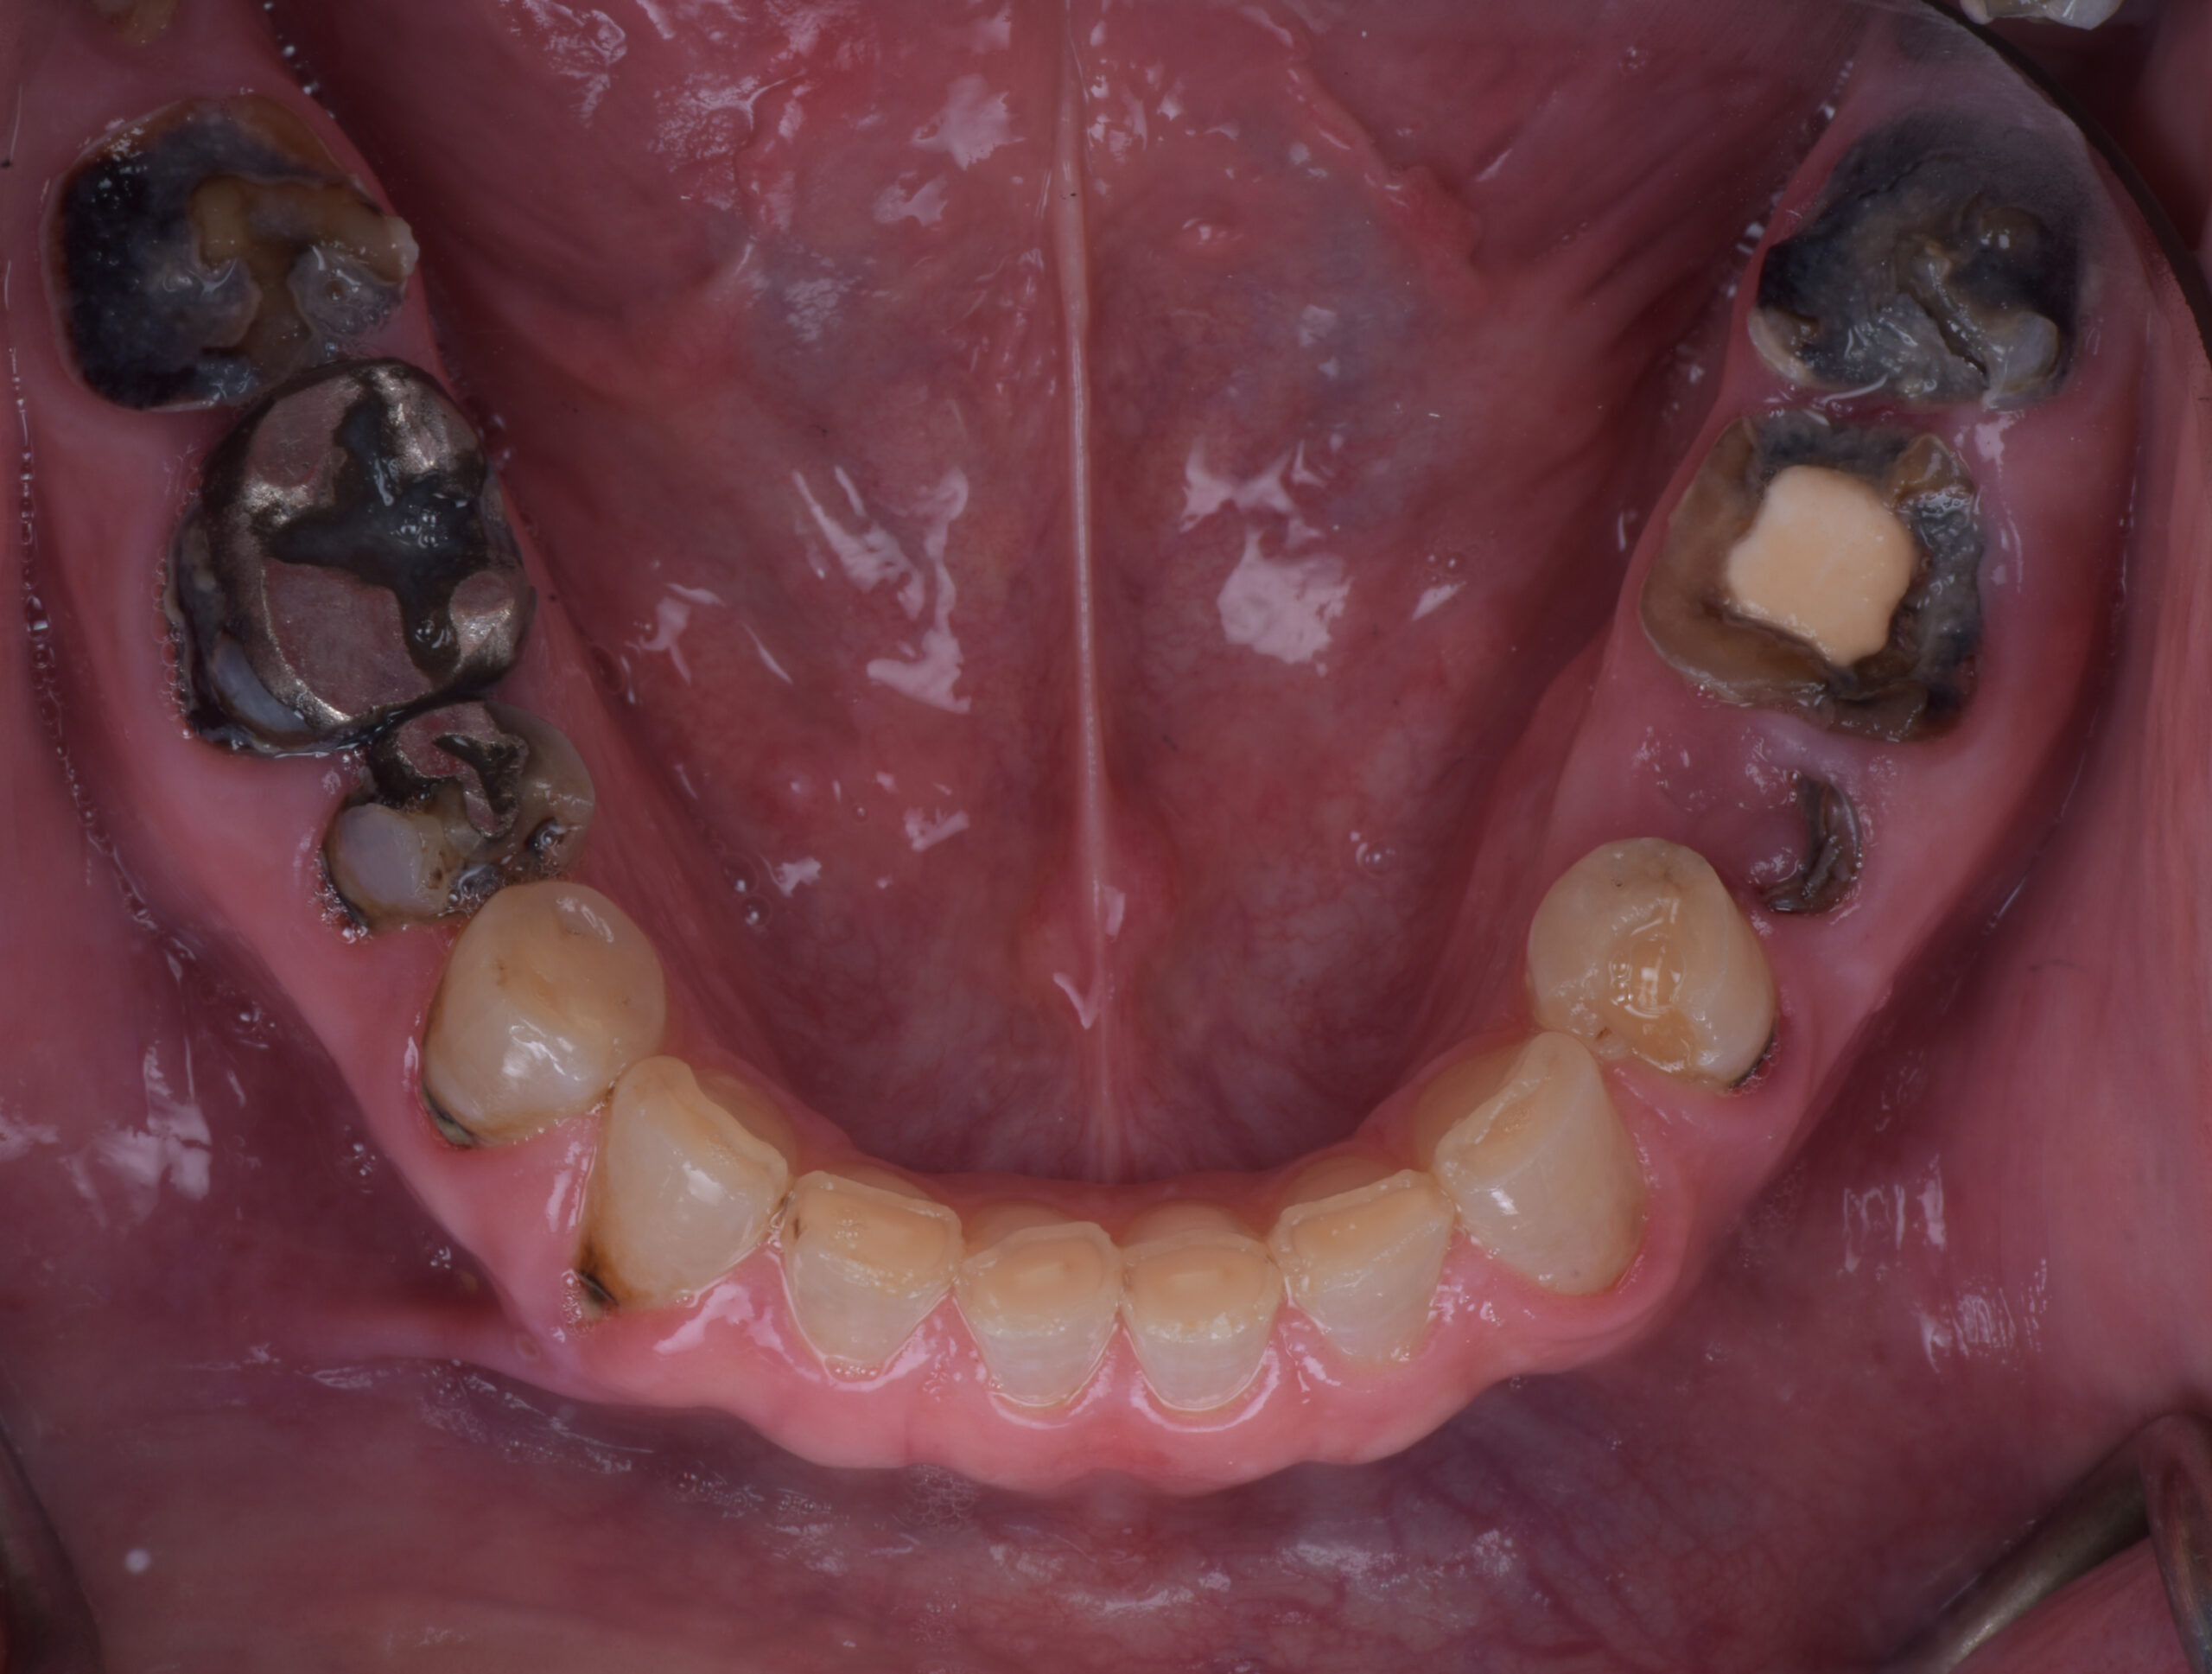

名古屋で歯がボロボロで抜歯と言われたときの確認点

名古屋で歯がボロボロと言われたとき、最初に確認したいのは「本数」ではなく「理由」です

名古屋で歯がボロボロで、何本も抜歯が必要と説明されたときに確認したいのは、抜く本数そのものではありません。

本当に整理すべきなのは、その歯が残せない理由と、残した場合にほかの歯へ何が起きるかです。

同じ「抜歯適応」でも、理由は大きく分かれます。

• 歯根破折で保存が難しい

• 重度の歯周病で周囲の骨が大きく失われている

• 虫歯が深く、被せ物の土台が作れない

• 感染が続き、隣の歯や噛み合わせに悪影響が出ている

• 口全体の治療設計上、残すほど不利になる

名古屋で歯がボロボロの状態から治療を考えるなら、抜歯の是非を一歯ずつではなく、全体の治療設計の中で判断することが大切です。